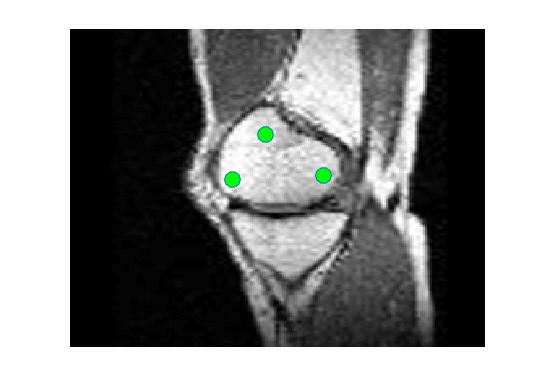

Four sets of test results are shown below. In Test 1 we compare models M1 – M6 to the proposed model M7 for two images which are hard to segment. The first is a CT scan from which we would like to segment the lower portion of the heart, the second is an MRI scan of a knee and we would like to segment the top of the Tibia. See Figure 9 for the test images and the marker sets used in the experiments. In Test 2 we will review the sensitivity of the proposed model to the main parameters. In Test 3 we will give several results achieved by the model using marker and anti-marker sets. In Test 4 we show the initialisation independence and marker independence of the Geodesic Model on real images.

Refer to captionRefer to captionRefer to captionRefer to caption

(i)                                 (ii)                                 (iii)                                 (iv)

Figure 9: Test 1 setting: (i) Image 1;  (ii) Image 1 with marker and anti-marker set shown in green and pink respectively;  (iii) Test Image 2; (iv) Image 2 with marker set shown.

In this test we give the segmentation results for models M1 – M7 for the two challenging test images shown in Figure 9. The marker and anti-marker sets used in the experiments are also shown in this figure. After extensive parameter tuning, the best final segmentation results for each of the models are shown in Figures 10 and 11. For M1 – M4 we obtain incorrect segmentations in both cases. In particular, the results of M2 and M4 are interesting as the former gives poor results for both images, and the latter gives a reasonable result for Test Image 1 and a poor result for Test Image 2. In the case of M2, the regularisation term includes the edge detector and the distance penalty term (see (4)). It is precisely this which permits the poor result in Figures 10(b) and 11(b) as the edge detector is zero along the contour and the fitting terms are satisfied there (both intensity and area constraints) – the distance term is not large enough to counteract the effect of these. In the case of M4, the distance term and edge detector are separated from the regulariser and are used to weight the Chan-Vese fitting terms (see (9)). The poor segmentation in Figure 11(b) is due to the Chan-Vese terms encouraging segmentation of bright objects (in this case), weighting ω𝜔\omega enforces these terms at all edges in the image and near \mathcal{M}. In experiments, we find that M4 performs well when the object to segment is of approximately the highest or lowest intensity in the image, however when this is not the case, results tend to be poor. We see that, in both cases, models M5 and M6 give much improved results to M2 and M4 (obtained by incorporating the geodesic distance penalty into each). The proposed Geodesic Model M7 gives an accurate segmentation in both cases. It remains to compare M5, M6 and M7. We see that M5 is a non-convex model (and cannot be made convex [39]), therefore results are initialisation dependent. It also requires one more parameter than M6 and M7, and an accurate set \mathcal{M} to give a reasonable area constraint in (4). These limitations lead us to conclude M6 and M7 are better choices than M5. In the case of M6, it has the same number of parameters as M7 and gives good results. M6 can be viewed as the model M7 with weighted intensity fitting terms (compare (18) and (30)). Experimentally, we find that the same quality of segmentation result can be achieved with both models generally, however M6 is more parameter sensitive than M7. This can be seen in the parameter map in Figure 12 with M7 giving an accurate result for a wider range of parameters than M6. To show the improvement of M7 over previous models, we also give an image in Figure 13 which can be accurately segmented with M7 but the correct result is never achieved with M6 (or M3). Therefore we find that M7 outperforms all other models tested M1 – M6.